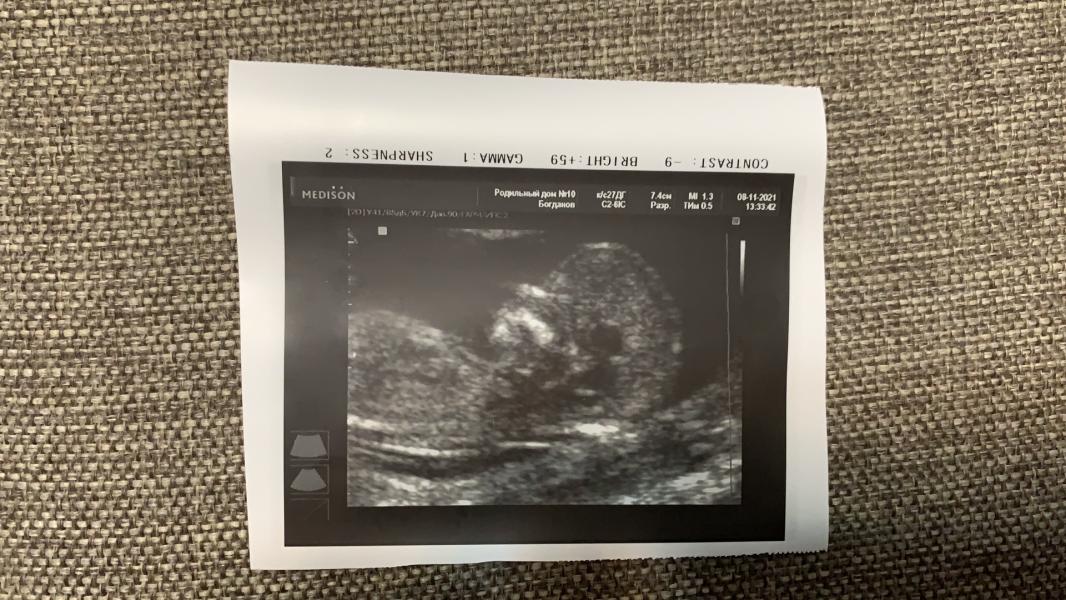

Нам уже 13 нд❤️

Растём🤞🤞🤞

Первый скрининг прошёл отлично, с малышом всё в порядке, кровь на патологии - хорошая, риски низкие и это не может не радовать 🤞❤️❤️